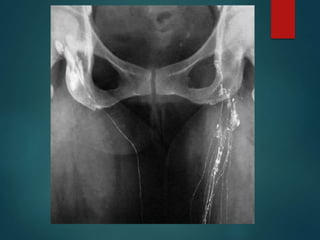

 Lymphangiography

INVESTIGATION OF LYMPHOEDEMA  ‘Routine’tests  Lymphangiography  Isotope lymphoscintigraphy  Computerised tomography  Magnetic resonance imaging  Ultrasound  Pathological examination